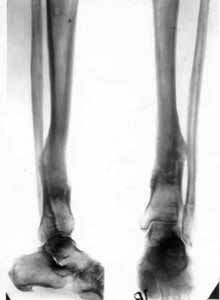

False joint of lower/third of shinbone.

Results of treatment.